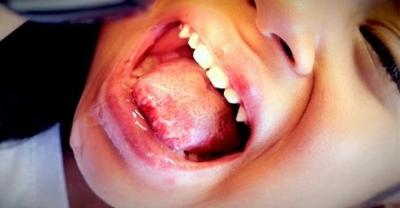

Фото 2. Одне з ускладнень після ангіни – стоматит, у такій ситуації бактерії від мигдалин поширюються далі по ротової порожнини, з-за чого утворюються виразки.

Патогенна мікрофлора спускається з горла і мигдаликів, вражає слизову оболонку рота. А також причиною буває грибкова інфекція, яка дуже часто виникає у зв’язку зі зниженням імунного захисту.

Виразки на мигдалинах можуть з’явитися вже після успішного одужання після ангіни. У такому разі їх появі сприяє низька активність імунітету і пригніченість природної мікрофлори.

Після важко перенесеної ангіни, можлива одна з рідкісних форм ускладнень, яка виражається у виникненні стоматиту у ротовій порожнині. Це трапляється у зв’язку зі зниженням місцевого імунітету.